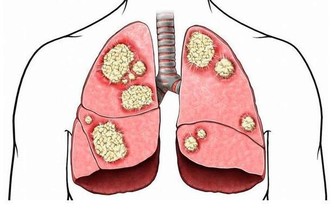

2.癌症

癌症也是這一年齡段高發的疾病,如肝癌、肺癌、乳腺癌、胃癌等。

3、X線檢查

4、CT檢查

CT檢查分辨率高,顯像清楚,可以在無症狀情況下發現某些特定器官的早期腫瘤,如肺癌的早期篩查等。